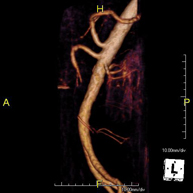

Prueba diagnóstica no invasiva que consiste en el estudio de la arteria aorta abdominal, obteniendo imágenes de alta definición anatómica mediante el empleo de un campo electromagnético y ondas de radio (con un emisor y un receptor). Es indispensable el uso de contraste paramagnético (Gadolinio). Sin embargo, no utiliza radiación ionizante. La calidad de las imágenes permite realizar reconstrucciones en 2D y 3D. Está indicado en aquellos pacientes con enfermedad vascular (aterosclerosis), estudio de aneurismas, en estudios pre-quirúrgicos de lesiones adyacentes a la aorta abdominal como "mapa" vascular, etc. - Angio RM Aorta-ilíaca

Prueba diagnóstica no invasiva que consiste en el estudio de la arteria aorta abdominal de las arterias ilíacas, obteniendo imágenes de alta definición anatómica mediante el empleo de un campo electromagnético y ondas de radio (con un emisor y un receptor). Es indispensable el uso de contraste paramagnético (Gadolinio). Sin embargo, no utiliza radiación ionizante. La calidad de las imágenes permite realizar reconstrucciones en 2D y 3D. Esta prueba está especialmente indicada como estudio pre-quirúrgico (mapa vascular) antes de intervenciones percutáneas o quirúrgicas de aorta abdominal y arterias ilíacas, estudio complementario en pacientes con isquemia de miembros inferiores, etc. - Angio RM Arterial extremidades inferiores

Prueba diagnóstica no invasiva que consiste en el estudio de la arteria aorta abdominal, obteniendo imágenes de alta definición anatómica mediante el empleo de un campo electromagnético y ondas de radio (con un emisor y un receptor). Es indispensable el uso de contraste intravenoso paramagnético (gadolinio). Sin embargo, no utiliza radiación ionizante. La calidad de las imágenes permite realizar reconstrucciones en 2D y 3D. Está indicado en aquellos pacientes con enfermedad vascular (aterosclerosis), estudio de aneurismas, en estudios pre-quirúrgicos de lesiones adyacentes a la aorta abdominal como "mapa" vascular… - Angio-RM Aorta iliaca

Prueba diagnóstica no invasiva que consiste en el estudio de la arteria aorta abdominal, obteniendo imágenes de alta definición anatómica mediante el empleo de un campo electromagnético y ondas de radio (con un emisor y un receptor). Es indispensable el uso de contraste intravenoso paramagnético (gadolinio). Sin embargo, no utiliza radiación ionizante. La calidad de las imágenes permite realizar reconstrucciones en 2D y 3D. Esta prueba está especialmente indicada como estudio pre-quirúrgico (mapa vascular) antes de intervenciones percutáneas o quirúrgicas de aorta abdominal, estudio complementario en pacientes con isquemia de miembros inferiores… - Angio-RM Arterias renales